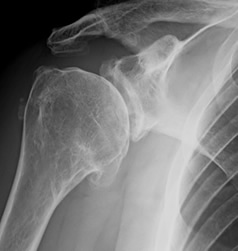

- Presenza di artrosi di spalla dovuta all’usura della cartilagine articolare della spalla (Fig. 6);

In questo caso (Fig. 10, 11, 12, 13) si evidenzia un quadro di grave artrosi della spalla in paziente con lesione dei tendini della cuffia dei rotatori e degenerazione del ventre muscolare della cuffia dei rotatori.